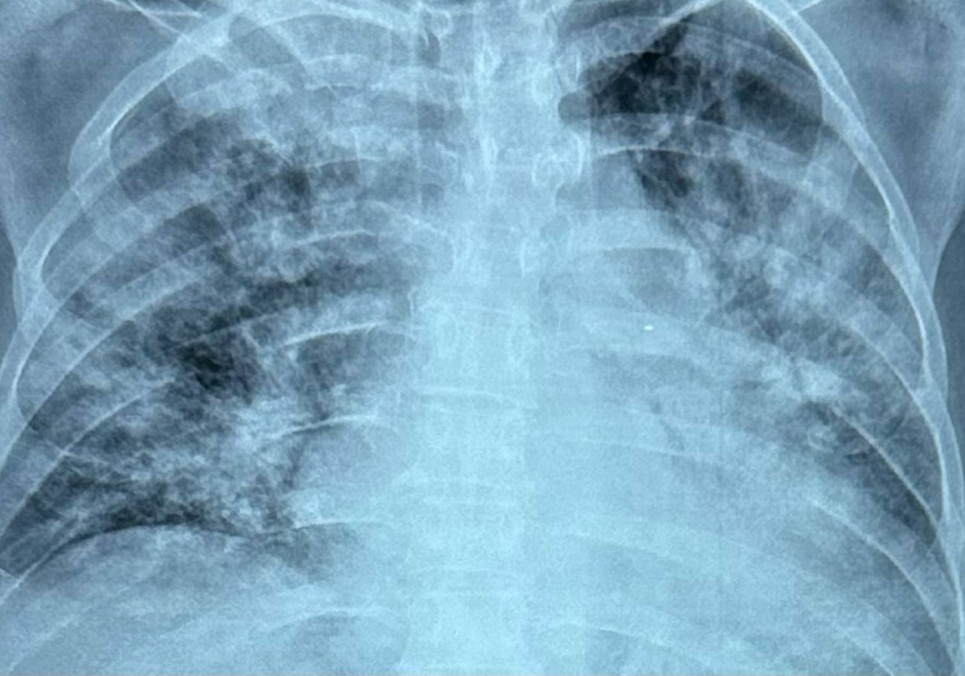

В Украине наблюдается значительное увеличение случаев гриппа, включая тяжелые формы, в том числе сочетанные с COVID-19. Об этом рассказала Ольга Голубовская, доктор медицинских наук, заслуженный врач Украины, заведующая кафедрой инфекционных болезней в Национальном медицинском университете имени А. А. Богомольца.

Инфекционист отмечает, что летальность растет, и все летальные случаи обусловлены отсутствием специфической терапии в первые дни болезни.